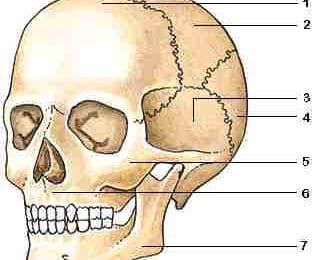

Jukbeen

De jukbeenderen (os zygomatica) vormen de wangen en de ...

Zeefbeen

De zeefbeendelen (pars os ethmoideus) bevinden zich tus...

Wiggebeen

Het wiggebeen is een van de schedelbeenderen en ligt la...

Voorhoofdsbeen

Het voorhoofdsbeen is een van de platte schedelbeendere...

Traanbeen

De traanbeentjes zijn twee van de kleinste botjes in he...